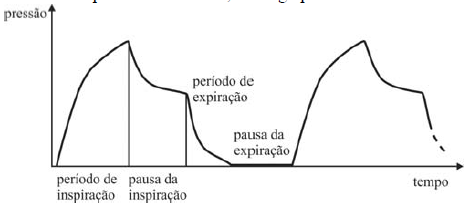

Abaixo, está representado um ciclo de ventilação pulmonar idealizado. Durante o início da inspiração, a pressão do gás dentro dos pulmões é mínima, havendo acréscimo da pressão interna e do volume com a entrada de ar. Assim que o pulmão está em sua capacidade máxima, há um período curto de pausa, em que trocas gasosas são realizadas a um volume constante, o que reduz a pressão. A pressão interna começa a decrescer à medida que há esvaziamento parcial da câmara, e atinge pressão mínima.

Internet: <www.livemedical.net/respiratory-mechanics> (com adaptações).

Entre as opções a seguir, assinale a que melhor representa o ciclo de ventilação descrito acima.